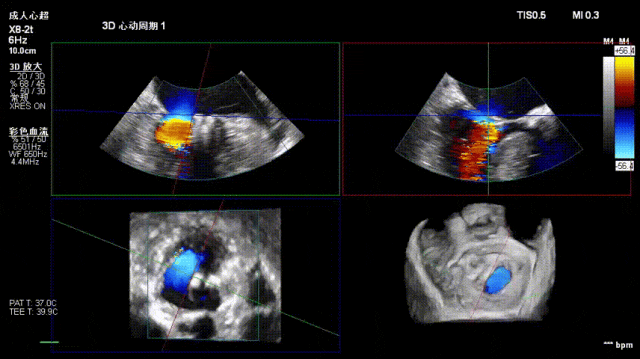

术后即刻反流降为少量,剩余瓣口面积2.57cm²,平均跨瓣压差2mmHg。

术后复查超声心动图显示:二尖瓣轻度返流,三尖瓣中度返流,二尖瓣可见金属夹回声,启闭正常;各心室大小正常,升主动脉不宽,主瓣回声增强,启闭良好;二尖瓣舒张期峰值流速1.4 m/s,功能面积2.1 cm²,跨瓣平均压差约4 mmHg。

术后心功能改善明显:LVdD 46mm,FS 33%,LA 45mm,LVDs 31mm,LVEF 62%。